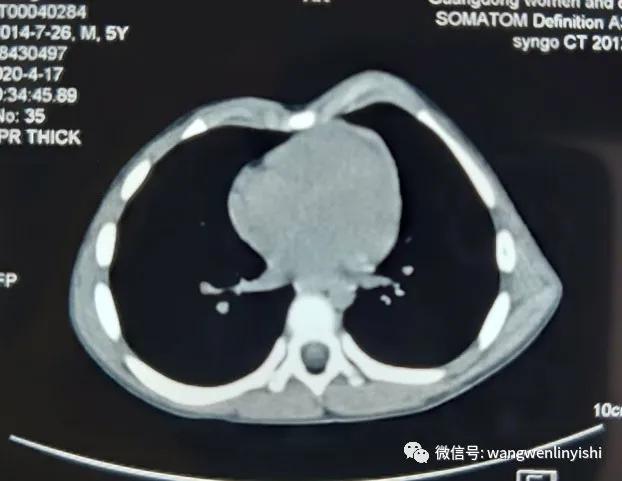

(术前的CT,左侧前胸壁突起,肋骨局部分叉)

入院查体:左侧前胸壁突起,局部可触及骨性结构前突,下部凹陷。影像学检查提示双侧胸壁具有肋骨分叉,但右侧体表无明显畸形。患者肋骨本身有畸形,而左侧胸壁外观为复合型畸形,既有突起又有凹陷,手术手术指征。经充分准备,今天上午实施手术。